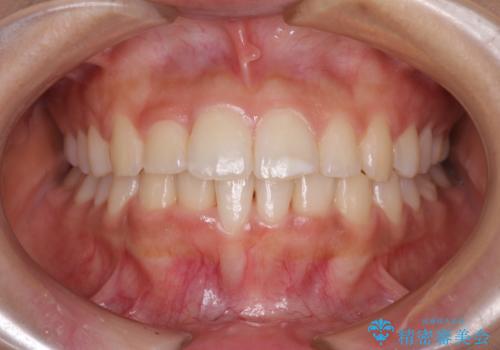

前歯の隙間を閉じたい 短期間でのワイヤー矯正

- 上の前歯の隙間を気にして来院された患者様です。

インビザラインの自己管理は自信がないとのことで、ワイヤー矯正により隙間を閉じていくこととしました。

下の前歯が上の前歯を突き上げるように咬合するため、咬み合わせの位置を改善しながら隙間を閉じていきました。

元々の歯並びが悪くなかったため、9ヶ月で綺麗に仕上がりました。

すきっ歯は後戻りを起こしやすいため、上下ともに歯の裏側を細いワイヤーで固定した上で、リテーナーのマウスピースを装着していただいています。